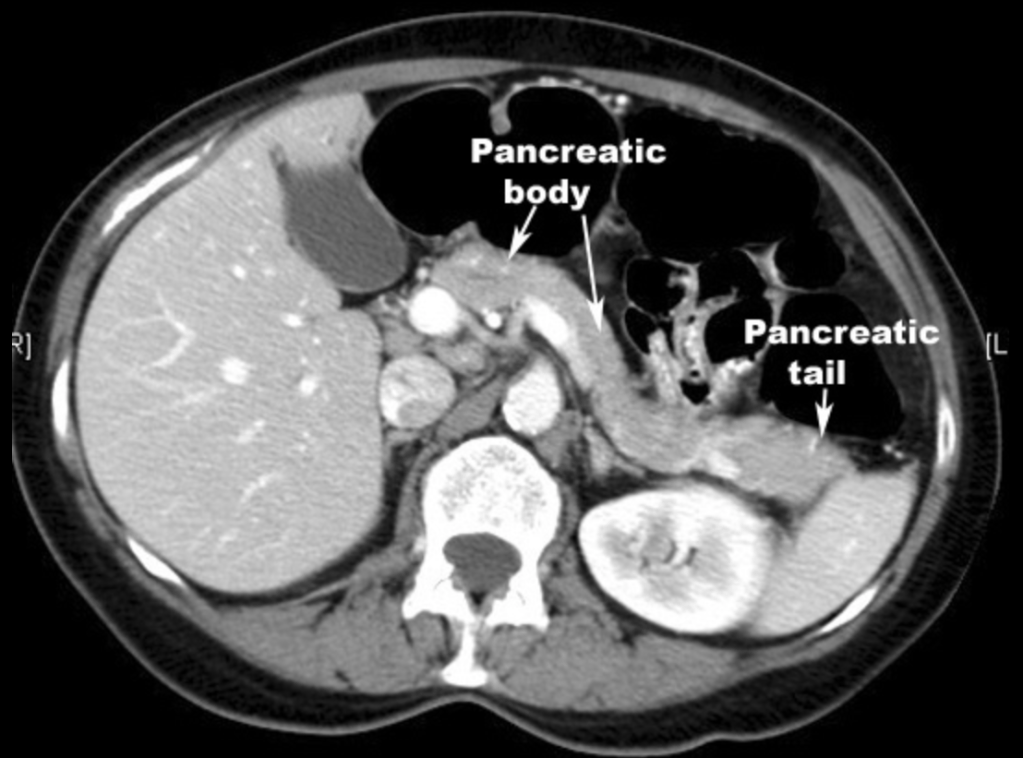

췌장의 몸통과 꼬리 부위가 하나의 영상절편에 놓여진 CT 횡단면영상입니다. 췌장의 꼬리는 언제나 예외없이 뒤쪽에 왼쪽 콩팥이 위치해있으며, 측면에는 비장이 존재합니다. 대부분은 비장의 아래쪽 부위가 췌장꼬리와 닿아있으며 20-30%정도에서는 좀 더 위쪽으로 올라와 비장의 hilum쪽과 닿아있지만, 초음파영상에서는 앞쪽에 존재하는 장관내공기음영에 가려져서 확인하기가 어렵습니다.

하지만, 췌장꼬리의 뒤쪽에 왼쪽 콩팥이 존재하는지 여부는 해당부위가 췌장꼬리가 맞다고 말할 수 있으려면 반드시 확인해줘야 합니다. 왜냐하면, 이 주변에는 초음파영상에서 췌장실질과 구분하기가 어려워 혼동할 수 있는 것들이 존재하기 때문입니다. 다름아닌 공장(jejunum) 및 내부의 공기에 의한 reverbration artifact나 왼쪽 콩팥 주변 및 후복막강의 지방조직이 췌장실질의 에코와 비슷해서 혼동하기 쉽기 때문입니다.

결론적으로 가장 중요한 점은 췌장꼬리를 확인할 때에는 췌장실질과 비슷한 에코를 가지고 있다고 해서 그것이 췌장이라고 착각하지 말고, 위치적으로 뒤쪽에 왼쪽 콩팥의 일부가 위치해있는 것을 확인한 후에 췌장꼬리부위를 확인했다고 체크해야 한다는 것입니다.